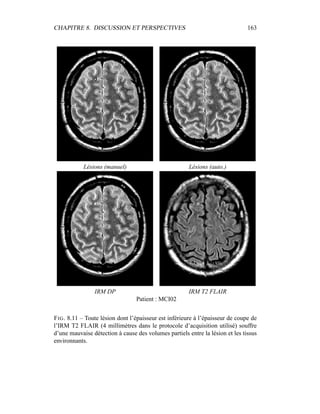

tière blanche, matière grise, LCR) du couple IRM T2/DP, sur lequel on a appliqué

un masque du parenchyme cérébral : visualisation de l’espace des intensités. La

variance de la classe LCR est très grande par rapport à celle de la classe matière

blanche : le modèle semble inadapté, car ces variances devraient être de taille